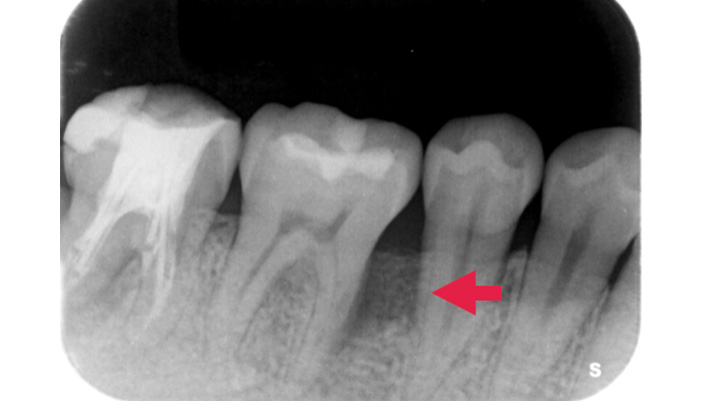

症例4

治療前

治療後

治療の経緯

初診時には、深い歯周ポケットや垂直性骨欠損、歯の動揺が認められました。まずは歯周基本治療を行い炎症の改善を図りましたが、歯周ポケットや骨の欠損が残存していました。このままでは歯の保存が難しくなる可能性があったため、歯を残すことを目的として歯周組織再生療法を選択しました。

| 主訴 | 歯周病が進行し、抜歯と言われた。 |

|---|---|

| 治療期間 | 1回 |

| 治療費 | ¥77,000 |

| 治療内容 | 歯周基本治療をし、改善が認められなかったため歯周外科手術を行い、歯周組織の再生を目的とした再生療法を行いました。 |

| 治療のリスク | 腫れ・痛み・感染などの可能性があります。 |